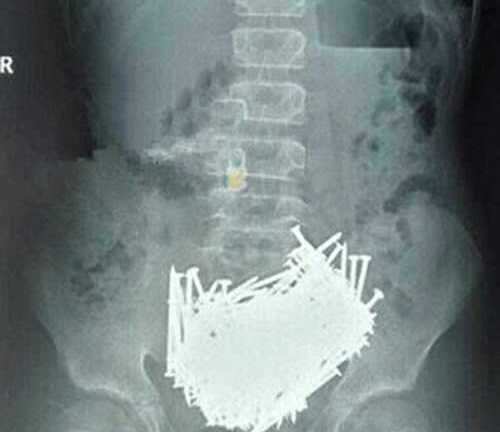

Mổ lấy hơn 200 cây đinh, tiền xu trong bụng cậu bé 15 tuổi

Một cậu bé mắc chứng bệnh nghiện ăn những thứ phi thực phẩm đã nuốt hàng trăm dị vật khủng khiếp vào bụng bao gồm đinh, đá, tăm xỉa răng và cả tiền xu.